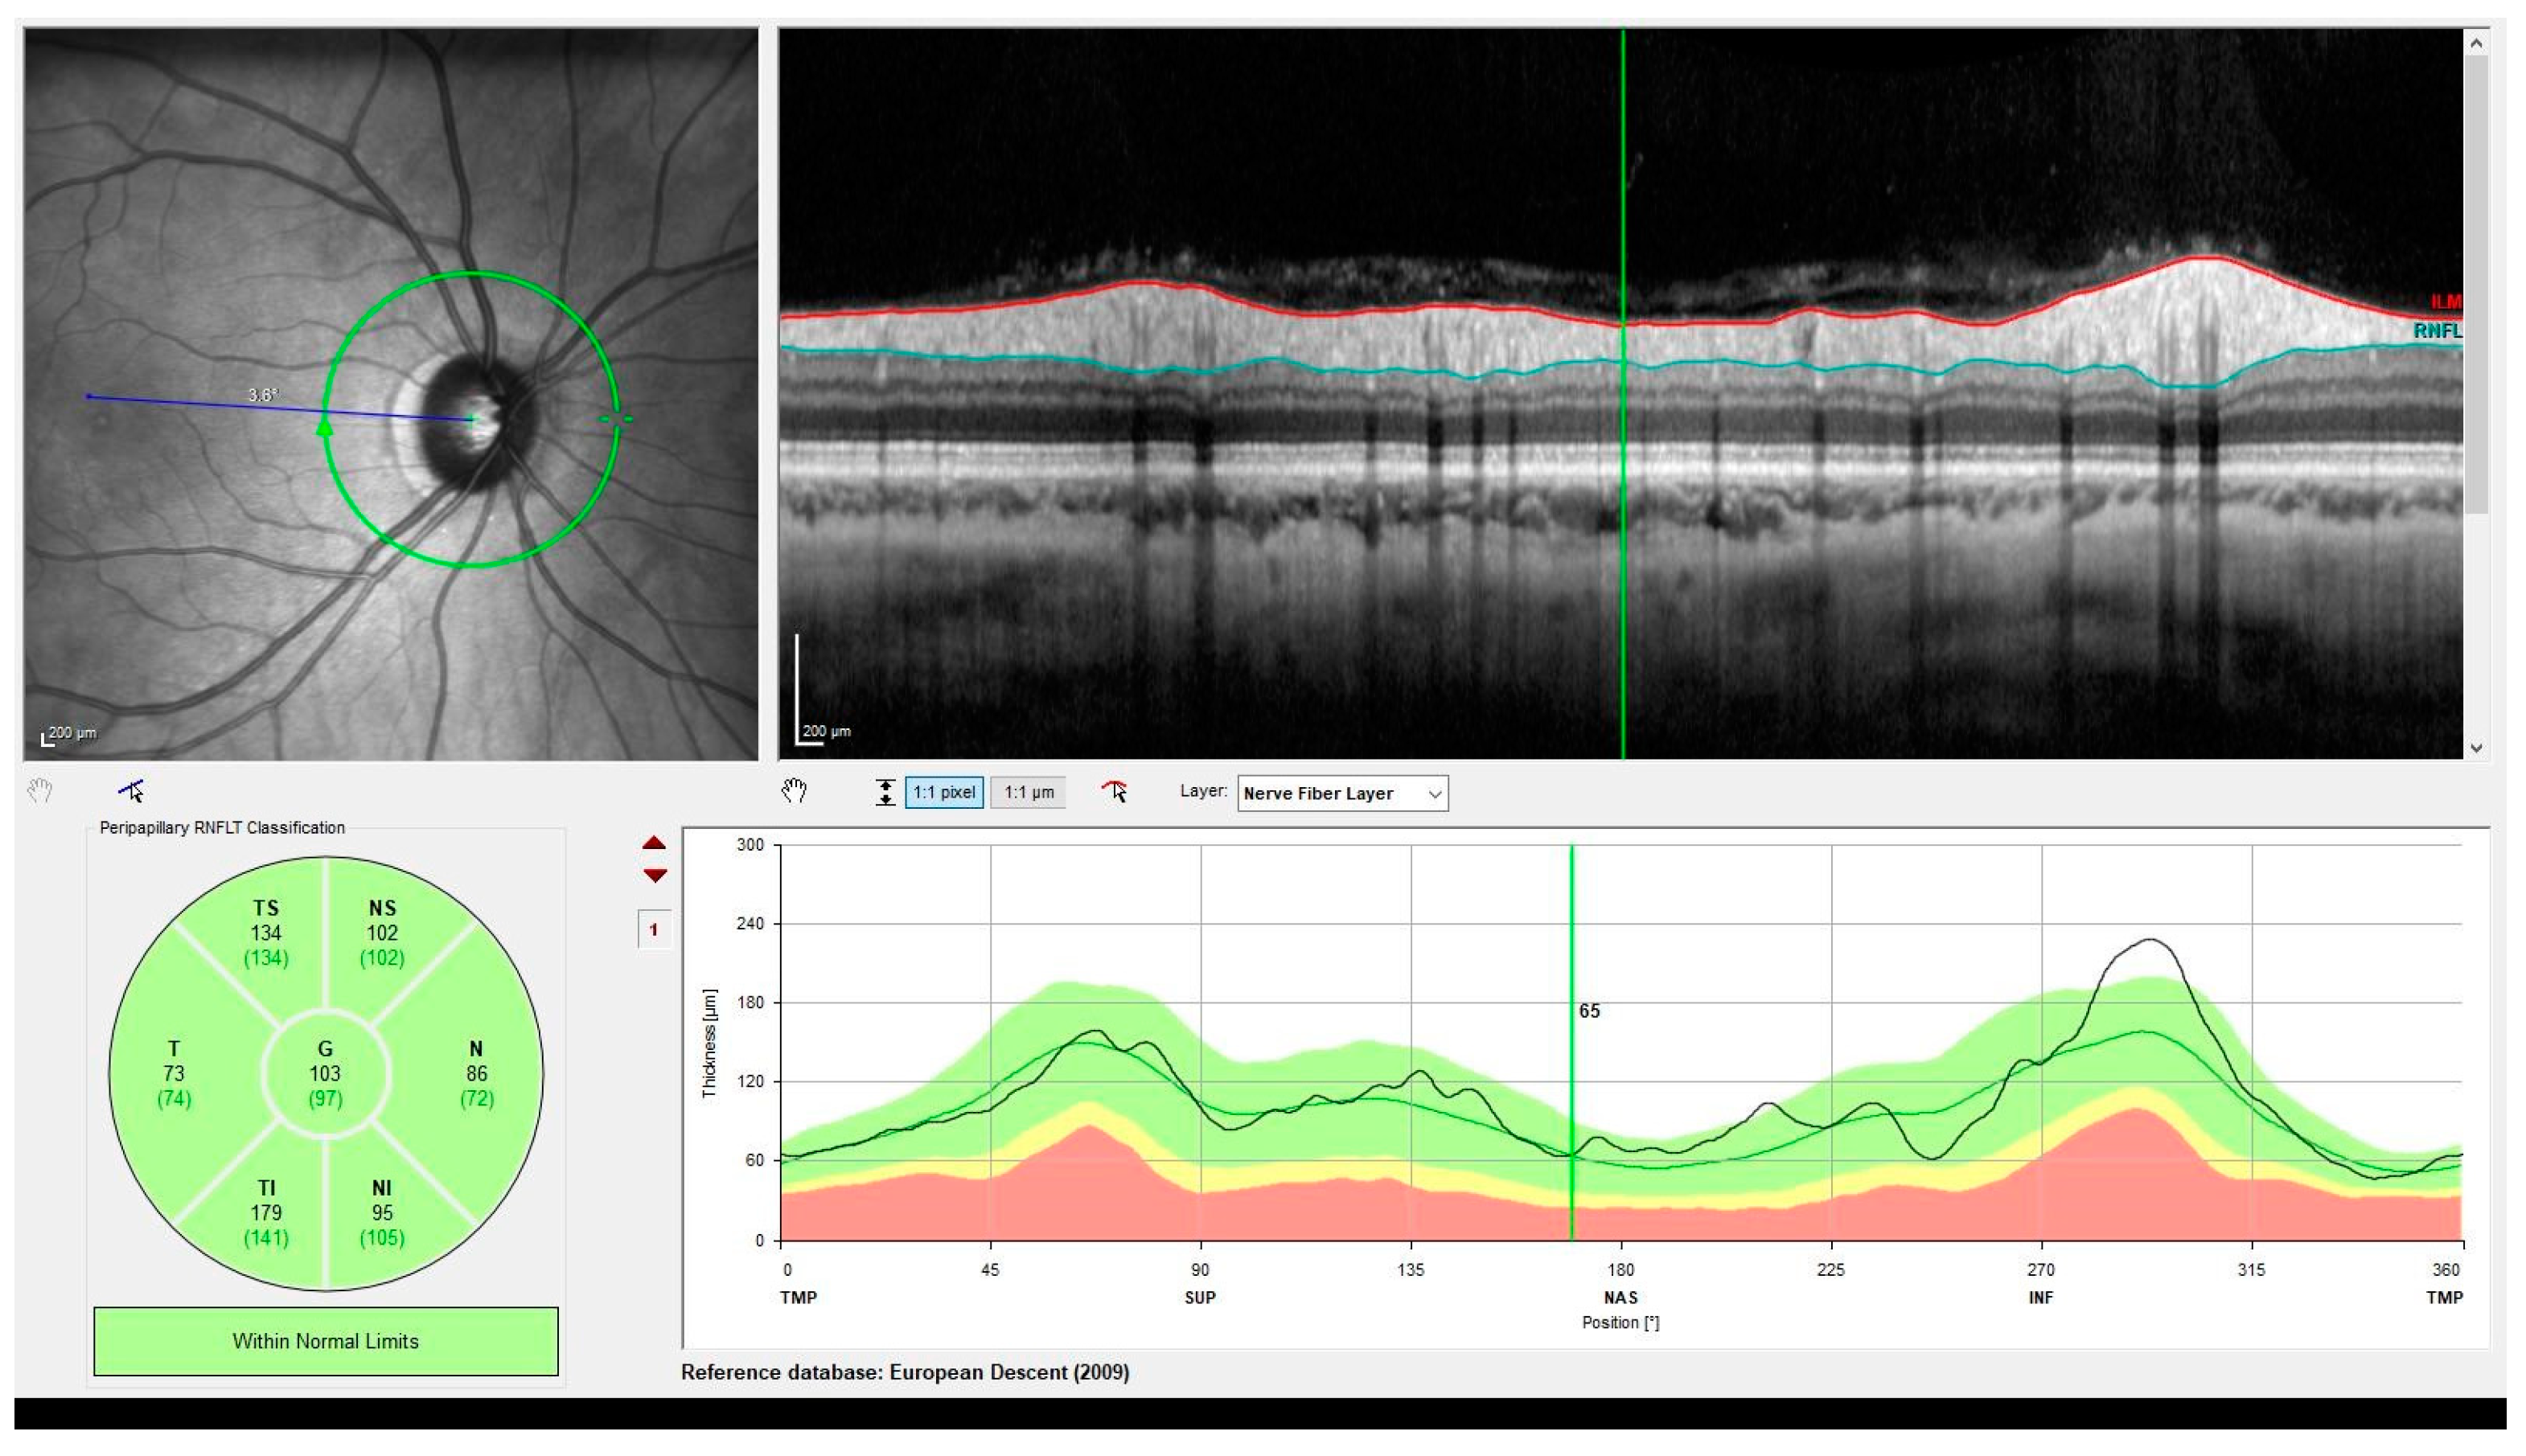

2. Optical Coherence Tomography

- Kersten, H.M.; Danesh-Meyer, H.V.; Kilfoyle, D.H.; Roxburgh, R.H. Optical coherence tomography findings in Huntington's disease: A potential biomarker of disease progression. J. Neurol. 2015, 262, 2457–2465. [Google Scholar] [CrossRef] [PubMed]

- Andrade, C.; Beato, J.; Monteiro, A.; Costa, A.; Penas, S.; Guimarães, J.; Reis, F.F.; Garrett, C. Spectral-Domain Optical Coherence Tomography as a Potential Biomarker in Huntington's Disease. Mov. Disord. 2016, 31, 377–383. [Google Scholar] [CrossRef]

- Schmid, R.D.; Remlinger, J.; Abegg, M.; Hoepner, R.; Hoffmann, R.; Lukas, C.; Saft, C.; Salmen, A. No optical coherence tomography changes in premanifest Huntington's disease mutation carriers far from disease onset. Brain Behav. 2022, 12, e2592. [Google Scholar] [CrossRef] [PubMed]

- Dusek, P.; Kopal, A.; Brichova, M.; Roth, J.; Ulmanova, O.; Klempir, J.; Preiningerova, J.L. Is retina affected in Huntington's disease? Is optical coherence tomography a good biomarker? PLoS ONE 2023, 18, e0282175. [Google Scholar] [CrossRef] [PubMed]